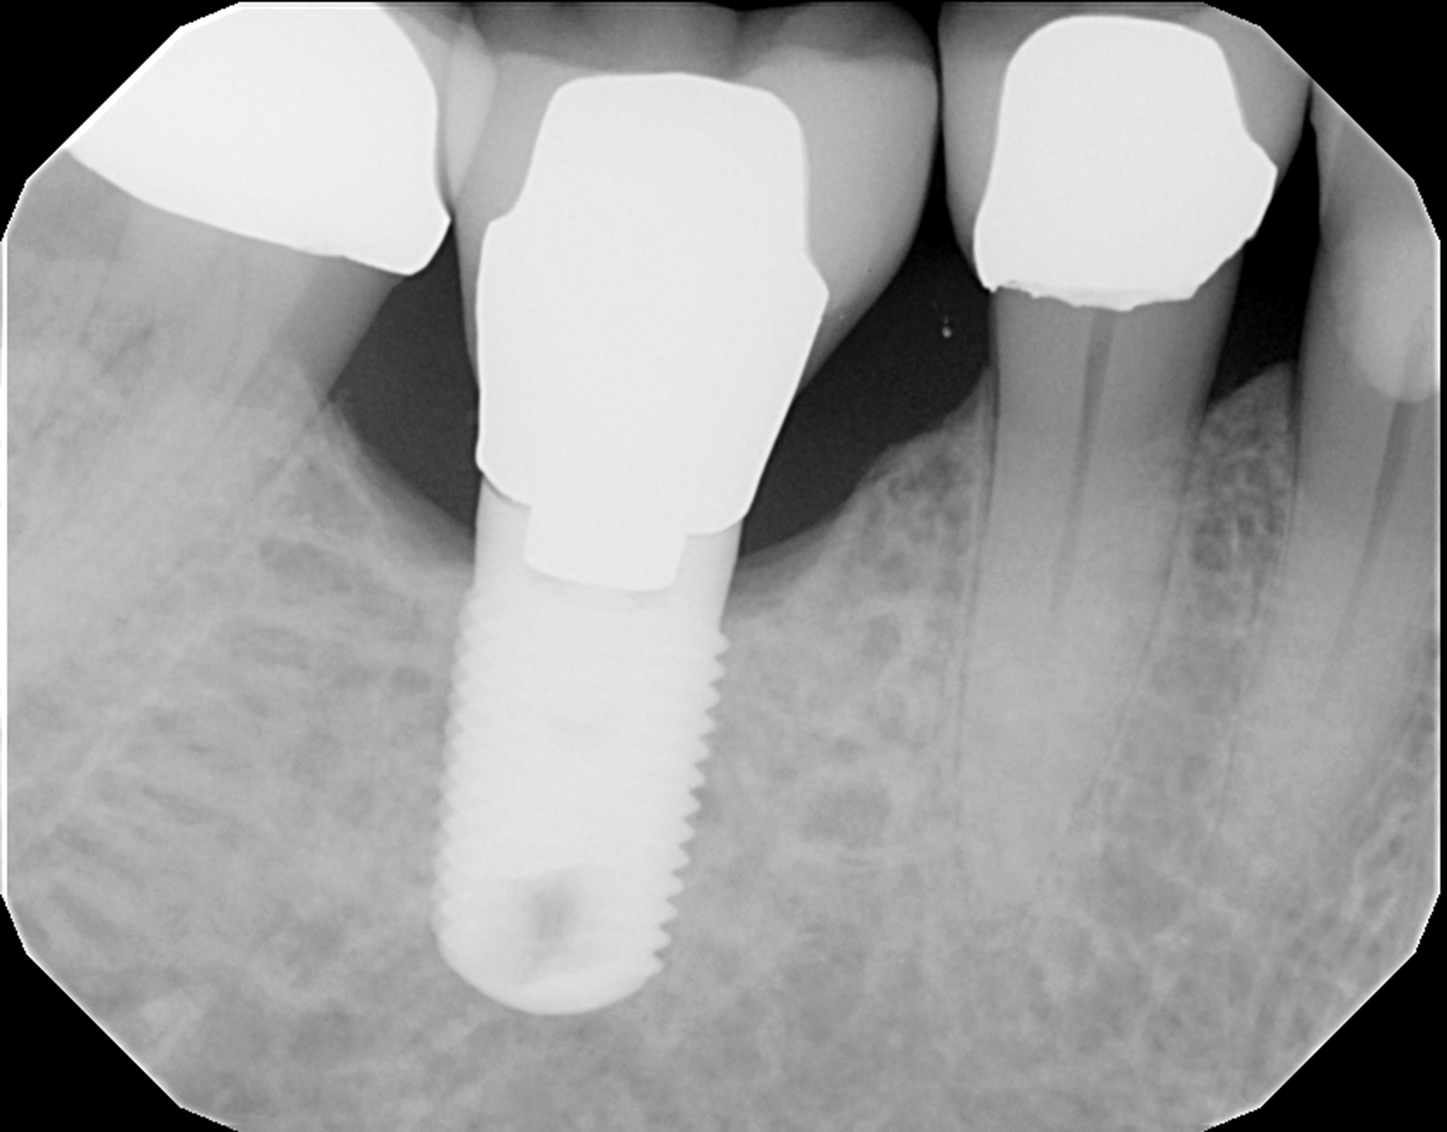

The patient's radiographic assessment, performed immediately following the initial clinical evaluation, included a panoramic radiograph (Figure 4) and bitewing and periapical radiographs of No. 30 (Figure 5). Panoramic findings showed generalized horizontal bone loss confined to the coronal third (15% to 20%), with circumferential bone loss, also referred to as "cupping," around both of the patient's implants, Nos. 30 and 13.

Fig 5. Periapical radiograph of implant No. 30, which helped in the evaluation of the extent of the cupping defect seen around the implant site.

Figure 5